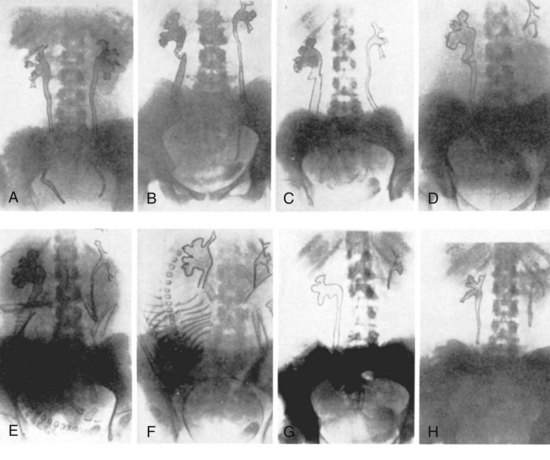

Recurrent UTIs are caused by either reemergence of bacteria from a site within the urinary tract (bacterial persistence) or new infections from bacteria outside the urinary tract (reinfection). Clinical identification of these two types of recurrence is based on the pattern of recurrent infections (Fig. 10–14). Bacterial persistence must be caused by the same organism in each instance, and infections that occur at close intervals are characteristic. Conversely, reinfections usually occur at varying and sometimes long intervals and often are caused by different species. The distinction between bacterial persistence and reinfection is important in management because patients with bacterial persistence can usually be cured of the recurrent infections by identification and surgical removal or correction of the focus of infection. Conversely, women with reinfection usually do not have an alterable urologic abnormality and require long-term medical management. Reinfections in men are uncommon and may be associated with an underlying abnormality, such as urethral stricture; therefore, at a minimum, endoscopic evaluation is indicated.

Once the bacteriuria has resolved (i.e., the urine shows no growth for several days after the antimicrobial agent has been stopped), recurrence with the same organism can arise from a site within the urinary tract that was excluded from the high urine concentrations of the antimicrobial agent. The 12 correctable urologic abnormalities that cause bacteria to persist within the urinary tract between episodes of recurrent bacteriuria are listed in Table 10–6. The relationship of these abnormalities to bacterial persistence, as well as the documentation that surgical excision removes the infection as a source of recurrent bacteriuria, is presented elsewhere in detail (Stamey, 1980). Once the urologist recognizes that the cause of the patient’s recurrent bacteriuria is bacterial persistence, Table 10–6 should serve as a checklist for known, correctable causes. Some of the causes are subtle, and many require cystoscopic localization of the infection with ureteral catheters to accurately define the focus of bacterial persistence.

Although patients with bacterial persistence are relatively uncommon, their identification is important because they represent the only surgically curable cause of recurrent UTIs. A systematic radiologic and endoscopic evaluation of the urinary tract is mandatory. CT and cystoscopy provide the initial screening. Retrograde urography may be required in selected patients to delineate abnormalities, such as diverticulum or nonrefluxing ureteral stump.

Urinary tract imaging will demonstrate the anatomy of the urinary tract and provide reasonable assessment of its functional status. In healthy women, upper tract abnormalities associated with reinfections are very rare; therefore routine urologic imaging is not indicated. Cystoscopy should be performed in men or women who have frequent reinfections and symptoms suggestive of obstruction, bladder dysfunction, and fistula. If the patient has residual urine that is judged to be significant (e.g., 100 mL) and due to a narrowing of the urethra, a single dilation of the urethra to improve bladder emptying would appear appropriate. There is little evidence, however, that repeated urethral dilation is indicated in the routine management of most women.